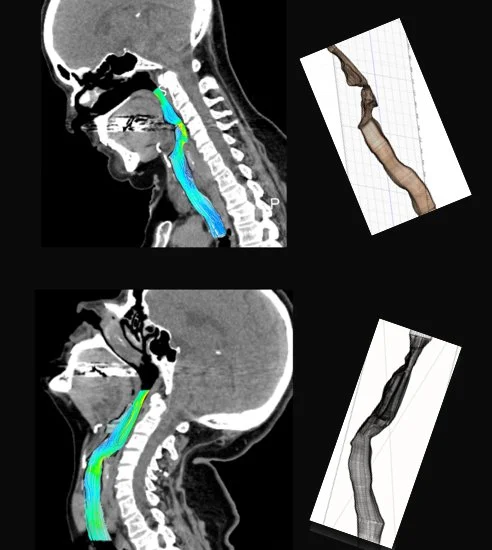

Click the artwork images below to find out more about each one.

Vote for your favourite artwork using this link - the winner will receive the People’s Choice Award during Art Week.